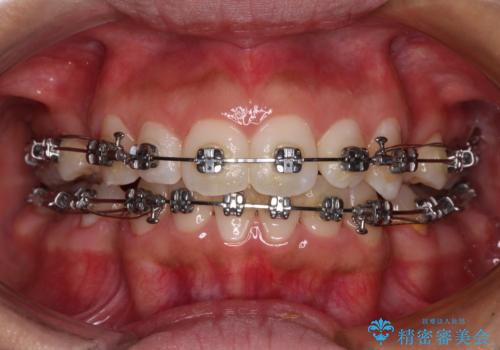

- 矯正装置

- メタルブラケット

- 出っ歯で唇が閉じにくいとのことで来院された患者様です。

顎先に力を入れないと唇が閉じきれない口元であったので、上下左右の第一小臼歯4本を抜歯して、ワイヤー装置にて矯正治療を行うこととしました。

費用を抑えるため、金属の装置を選択されました。